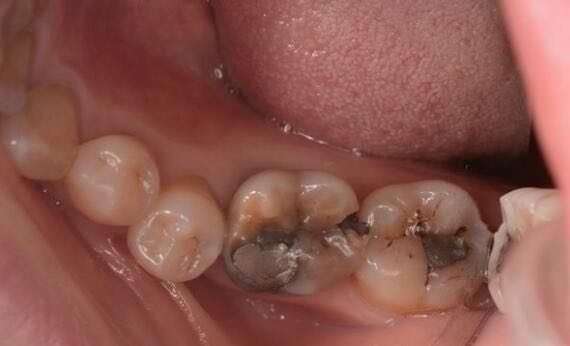

术后形态恢复好,患者满意。